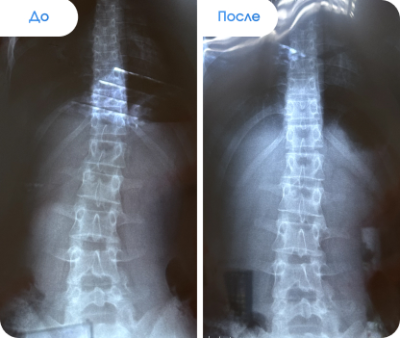

Результаты наших пациентов

✔ После процедуры «Антиспазм подзатылочных мышц» сколиоз II степени перешел на I степень.